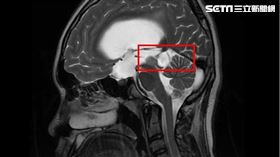

15歲男頭痛昏倒 竟是水腦併中腦腫

15歲男孩因頭痛不適昏倒,被家人緊急送醫,經急診診斷...